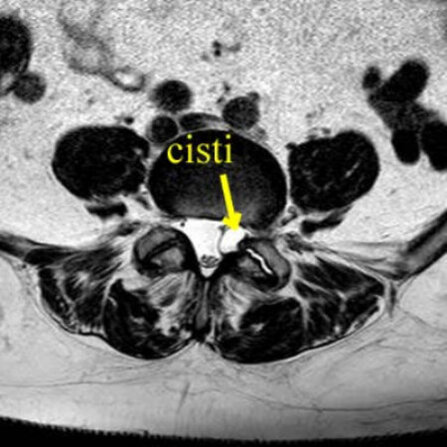

Una risonanza lombare ha evidenziato cisti sinoviale a ridosso della radice nervosa a livello L4-L5 sinistra.

Non presentava disturbi di forza all’esame neurologico obbiettivo.

Optava per ozonoterapia.

Nel corso delle sedute (effettuate alcunecon tecnica ecoguidata iuxtaradicolare L4-L5 graduale diminuzione del dolore sciatico.

Alla fine delle 8 sedute (4 settimane di trattamento), regressione completa del dolore alla gamba sinistra, con possibilità completa di mobilizzazione e graduale ritorno alla normalità.

A distanza di 4 mesi ha effettuato una nuova risonanza magnetica lombare, che ha documentato la completa scomparsa della cisti sinoviale.

Anche in questo caso non è dimostrabile l'esclusivo rapporto tra ozonoterapia ecoguidata e la scomparsa della cisti sinoviale.